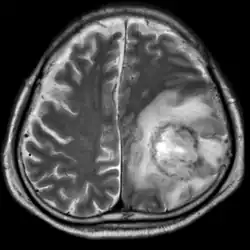

| T2-weighted MRI showing a necrotic brain abscess caused by Acanthamoeba. | |

B: T1-weighted MRI showing expansion of the brain infection 4 days later